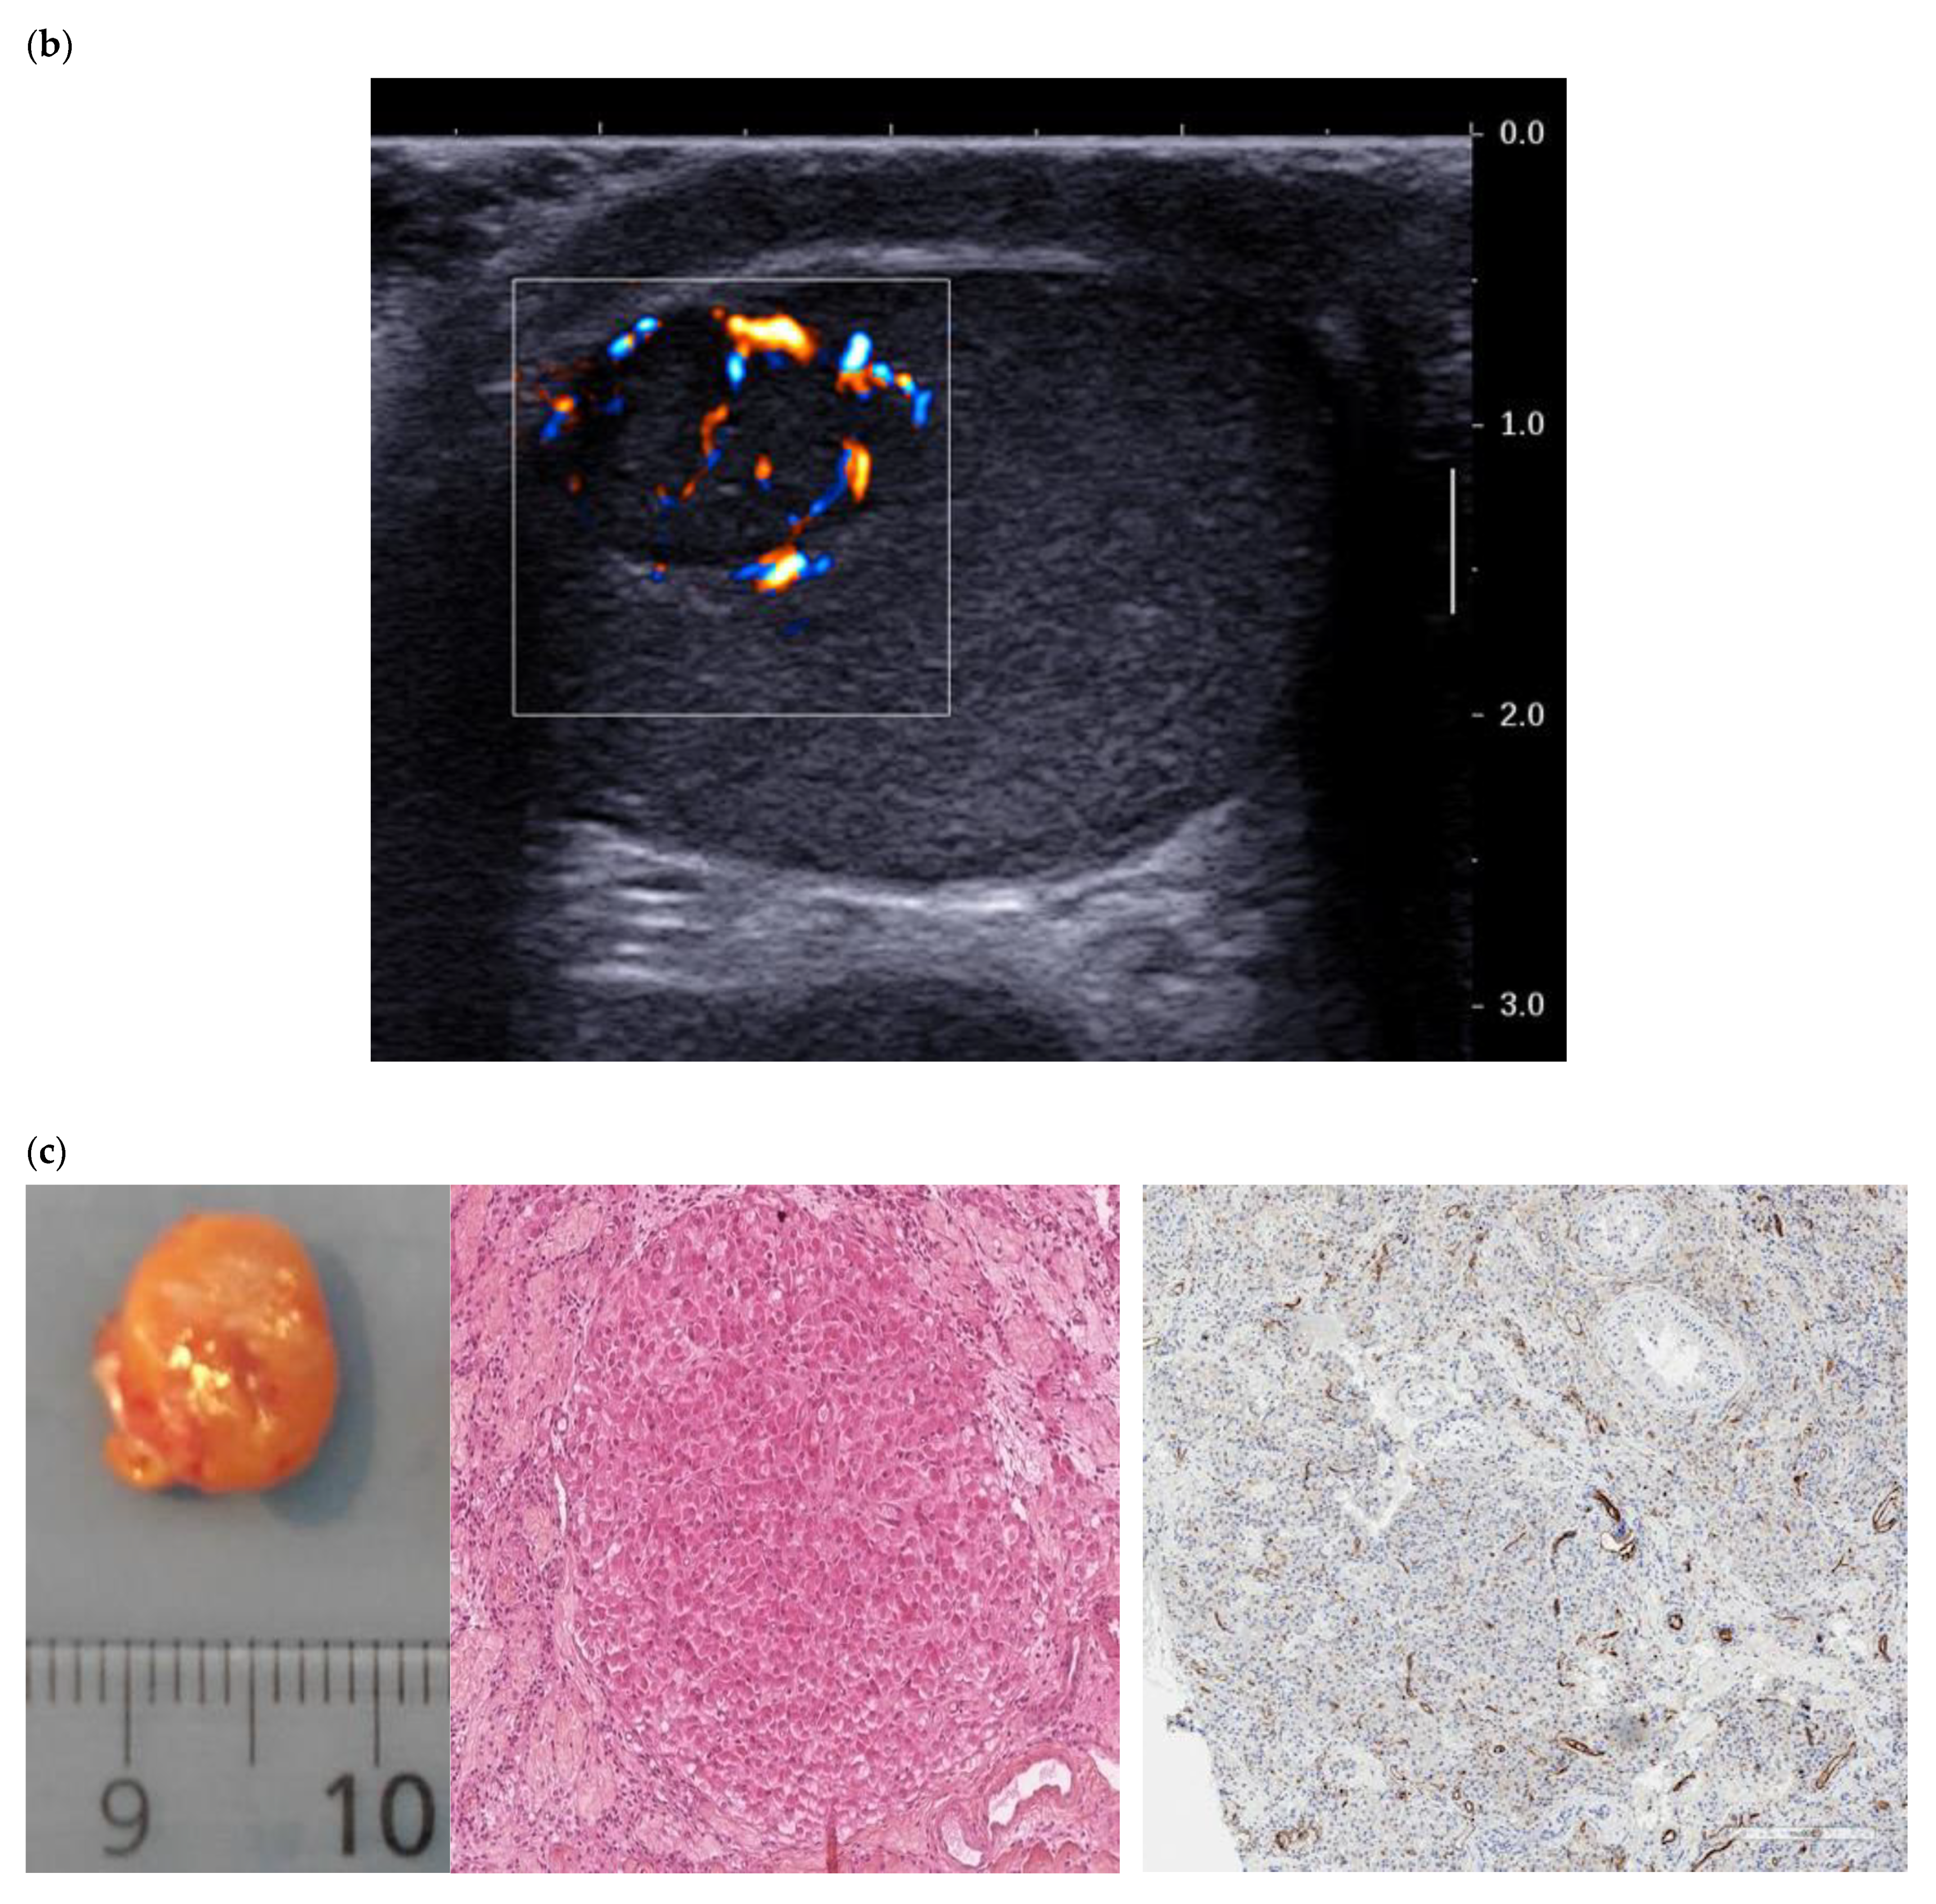

3.2. Color Doppler and Ultrasensitive Doppler

3.4. Elastography